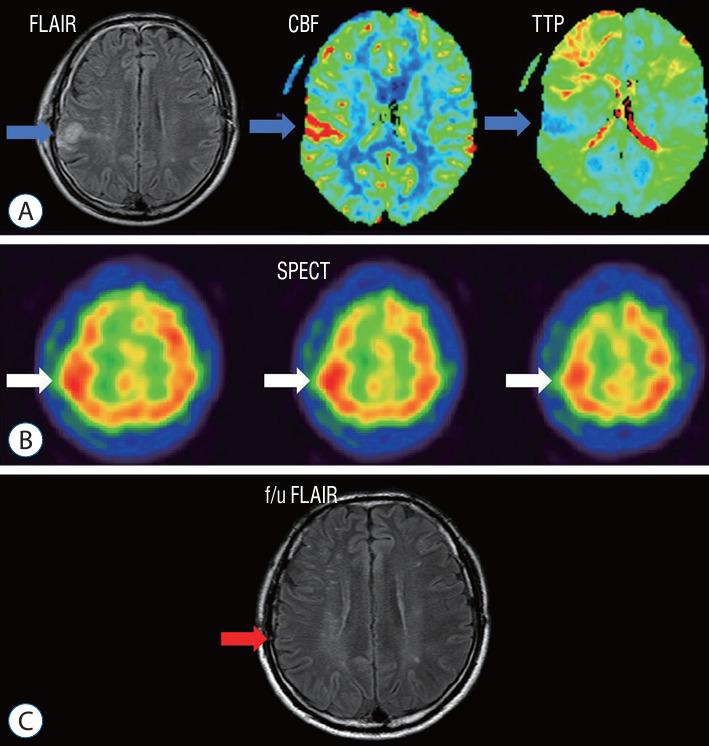

A retrospective study was performed of patients who underwent STA-MCA anastomosis due to Moyamoya disease or atherosclerotic steno-occlusive disease. A protocol aimed at preventing CHS was instituted, leveraging the use of MRI FLAIR. Patients underwent MRI diffusion with FLAIR imaging 24 hours after STA-MCA anastomosis. A high signal on FLAIR images signified the presence of hyperemia at the bypass site, triggering a protocol of hyperemia care. All patients underwent hemodynamic evaluations, including perfusion MRI, single-photon emission computed tomography (SPECT), and digital subtraction angiography, both before and after the surgery. If a high signal intensity is observed on MRI FLAIR within 24 hours of the surgery, a repeat MRI is performed to confirm the presence of hyperemia. Patients with confirmed hyperemia are managed according to a protocol aimed at preventing further progression.

Out of a total of 162 patients, 24 individuals (comprising 16 women and 8 men) exhibited hyperemia on their MRI FLAIR scans following the procedure. SPECT was conducted on 23 patients, and 11 of them yielded positive results. All 24 patients underwent perfusion MRI, but nine of them showed no significant findings. Among the patients, 10 displayed elevations in both CBF and cerebral blood volume (CBV), three only showed elevation in CBF, and two only showed elevation in CBV. Follow-up MRI FLAIR scans conducted 6 months later on these patients revealed complete normalization of the previously observed high signal intensity, with no evidence of ischemic injury.